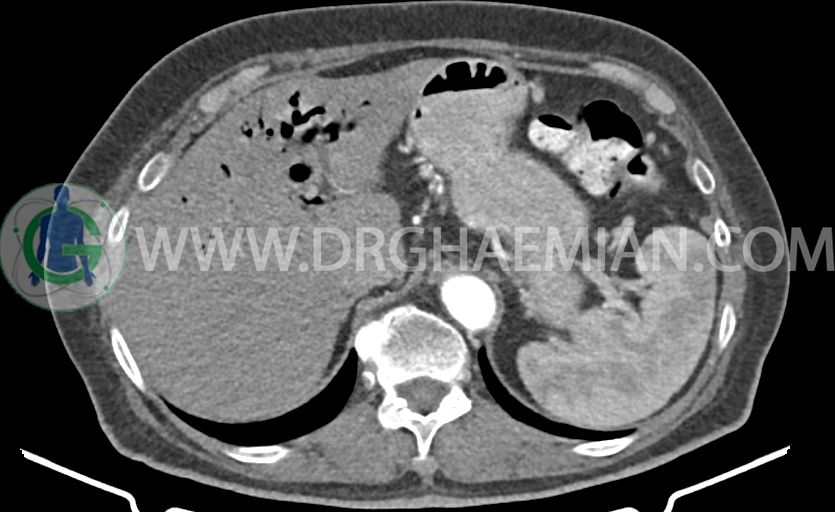

در سی تی اسکن اسپیرال شکم و لگن با و بدون کنتراست خوراکی و وریدی- پروتکل پانکراس (مولتی دیدکتور 16 با مقاطع ظریف و بازسازی های ساژیتال و کرونال) :

ضایعه ای در کبد، طحال، کلیه راست و آدرنالها مشهود نیست.

کلیه ها کنتراست را ترشح کرده اند و نمای سیستم پیلوکالیسیل و حالب راست نرمال است .

ضایعه ای در روده باریک و کولون مشهود نیست .

– اتروفی دیستال پانکراس (بدون تغییر نسبت به سی تی اسکن 1401/9/17)

-Fat stranding در اطراف پانکراس و فضاهای مزانتر در Mid line و Mid abdomen